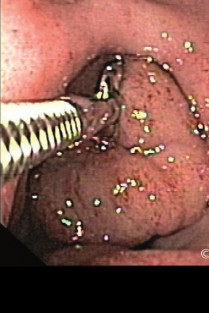

- Endoscopie respiratoire (Module 1, niveau 1) Être capable de citer les indications, contre-indications, apports et limites de l’endoscopie respiratoire. De choisir à bon escient le matériel à utiliser en adaptant ses caractéristiques à l’indication. D’entretenir ce matériel. De pratiquer l’exploration du tractus respiratoire d’un mammifère. De reconnaître les aspects normaux des cavités nasales, du larynx, de la trachée et des bronches. De réaliser des biopsies nasales, des prélèvements pulmonaires par cytobrosse et un lavage broncho-alvéolaire. Endoscopie digestive (Module 2, niveau 1) Être capable de citer les indications, contre-indications, apports et limites de l’endoscopie digestive. De choisir à bon escient le matériel à utiliser en adaptant ses caractéristiques à l’indication. D’entretenir ce matériel. De pratiquer l’exploration du tractus digestif d’un mammifère monogastrique. De reconnaître les aspects normaux du tractus digestif. De réaliser des biopsies des muqueuses digestives.